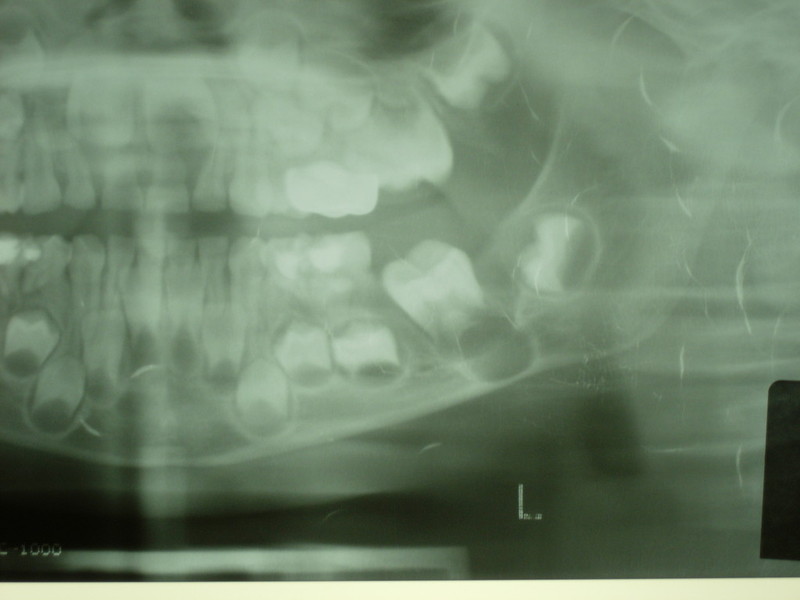

Cyst Associated with an Impacted Tooth in a Child